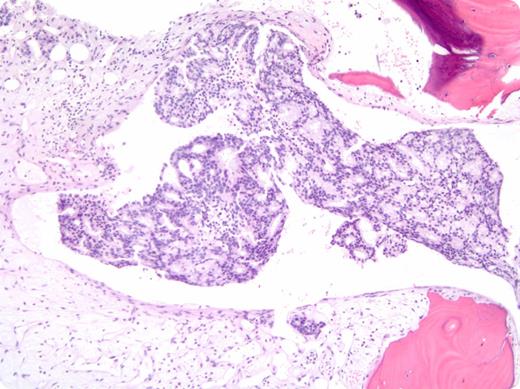

A 47-year-old African American man presented with lightheadedness and exertional dyspnea. Laboratory work revealed: hemoglobin, 2.9 g/dL; platelets, 17 × 109/L; and lactate dehydrogenase, 1492 IU/L. Folate, B12, and coagulation studies were normal. His peripheral smear showed increased schistocytes, polychromasia, and nucleated red blood cells. The patient was started on plasma exchange for presumed thrombotic thrombocytopenic purpura (TTP). However, his hematologic parameters failed to improve, and his pretreatment ADAMTS13 activity of 54% prompted further evaluation. A bone marrow biopsy demonstrated diffuse infiltration by adenocarcinoma, positive for prostate-specific antigen (PSA) and CK19 by immunohistochemistry, consistent with a diagnosis of metastatic prostate cancer. His serum PSA was elevated at 1162 ng/mL, and imaging revealed retroperitoneal lymphadenopathy with scattered bone lesions. The patient was started on combined androgen blockade with bicalutamide and leuprolide. After 8 weeks of treatment, his platelet count normalized and his hemoglobin improved to 10 g/dL.

Bone marrow involvement by metastatic carcinoma is uncommon and typically represents a late manifestation of disease. Marrow infiltration can lead to intramedullary hemolysis with significant cytopenias and schistocytes on peripheral smear, mimicking TTP. In this case, the patient’s hematologic manifestations were the presenting features of his malignancy, creating a diagnostic dilemma.